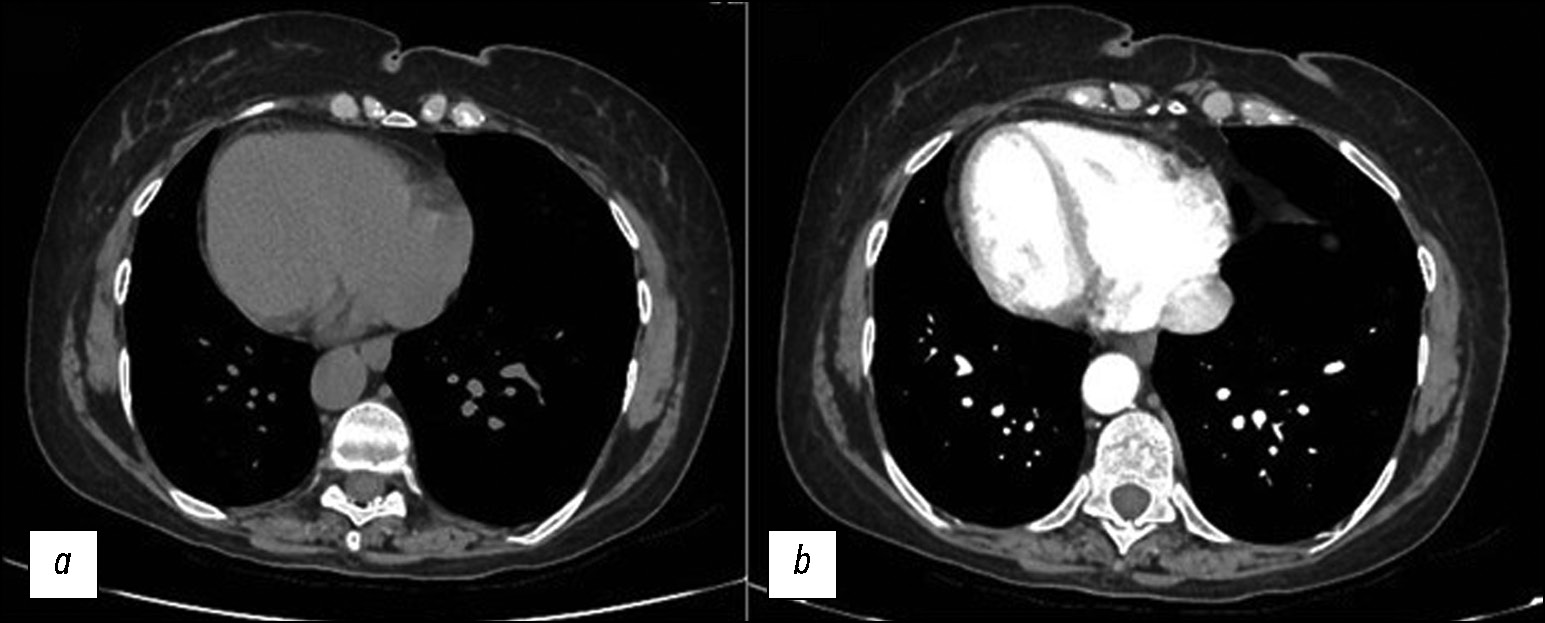

Fig. 2. Axial CT images of the abdomen without (a) and with contrast medium (b) show SIT and some calcific calculi in the gallbladder. The stomach and spleen are on the left, and the bigger lobe of the liver is on the right.

Fig. 3. Axial CT image without (a) and with contrast medium (b) that shows the stomach on the right side.